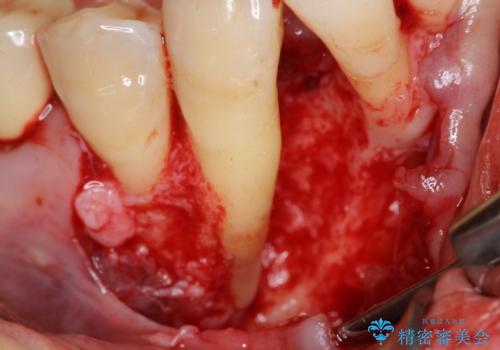

- 銀の詰め物が気になるとのことで来院。

2本隣り合っているつめものを、同時にやりかえをしました。

向かい合う銀歯を同時にやり変えることで、コンタクト(歯と歯の間の形)を理想的に仕上げることができ、ものも挟まりにくいように仕上げることができます。